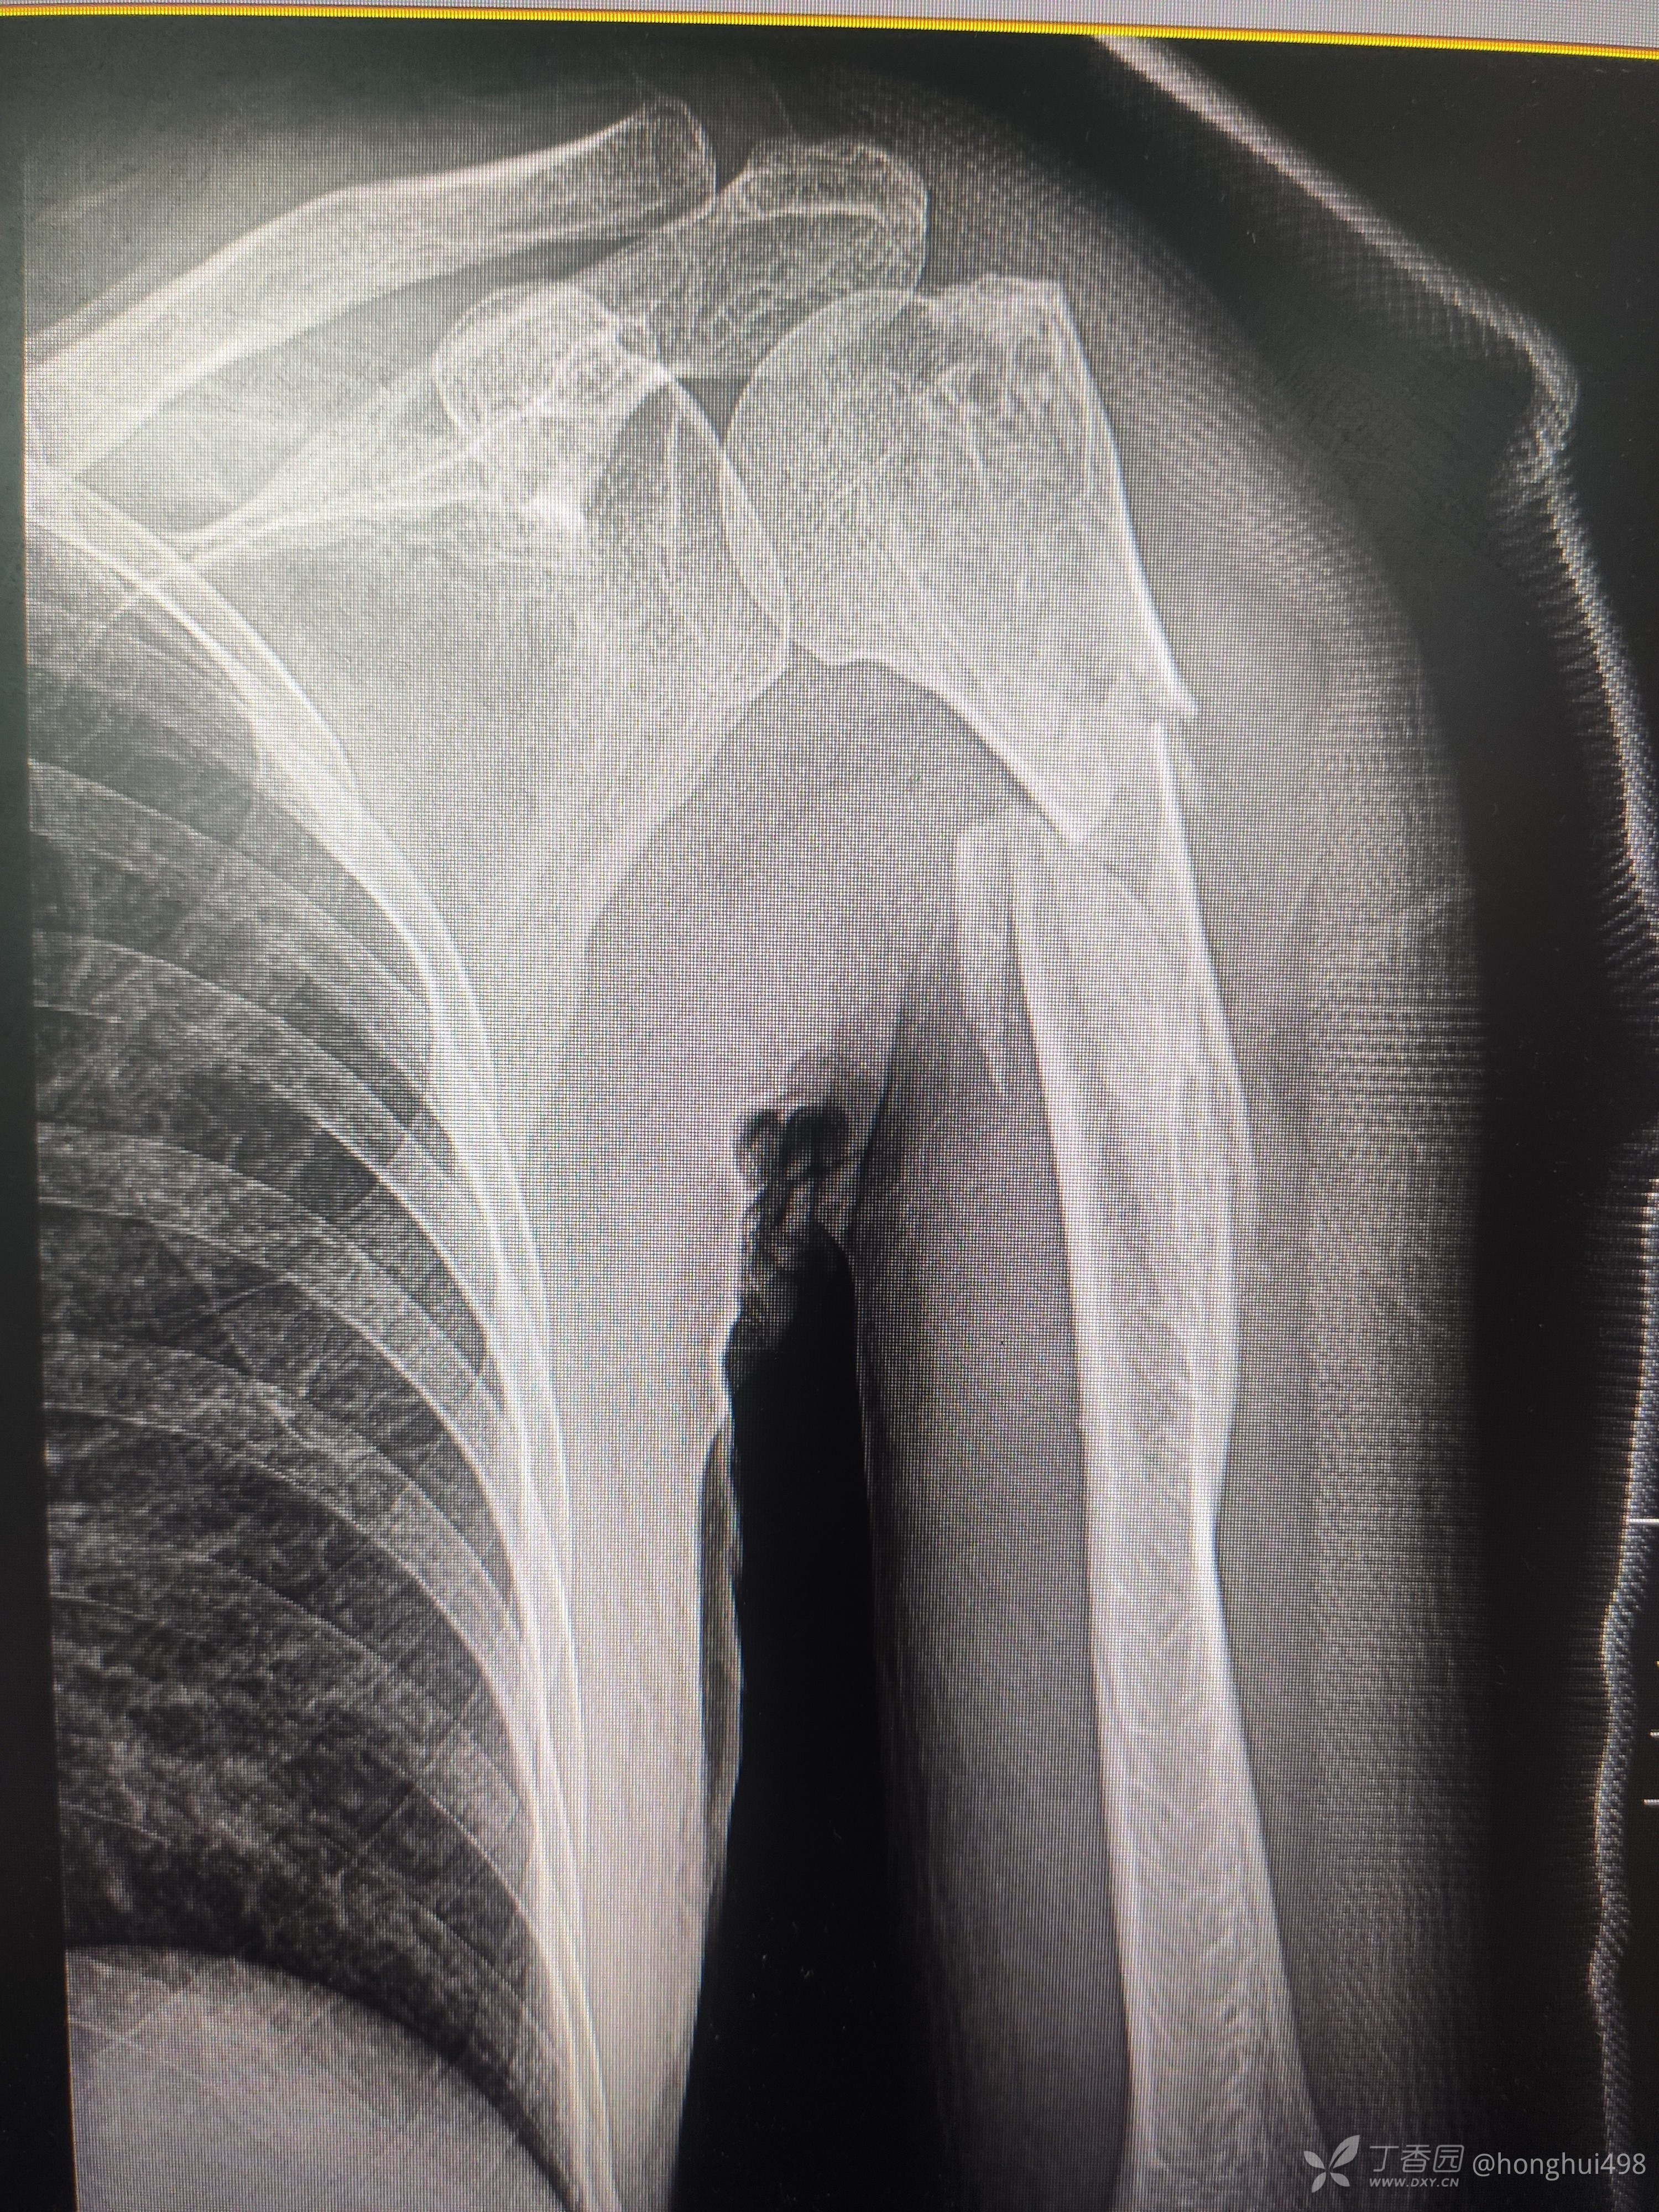

男性患者,62岁,摔倒致伤,入院诊断右肱骨骨折。麻醉下行肱骨骨折有限切开复位髓内钉+钢缆固定。

肱骨髓内固定做得比较少,但是手术还是顺利,此例患者你们如何选择固定方式?欢迎讨论